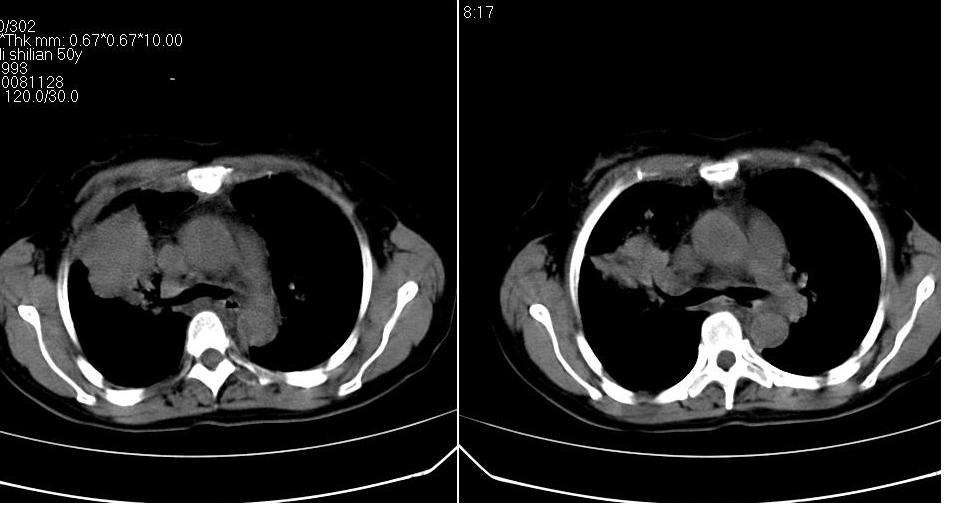

标题: CT16839:胸部CT平扫

女 50岁,在其他医院确诊肺癌.

肺癌并肺及纵隔转移

都已发生广泛转移了,意义不大。

支持 右肺上叶肺癌并两肺及纵隔转移。

考虑 肺癌伴肺及纵隔转移,心包膜增厚